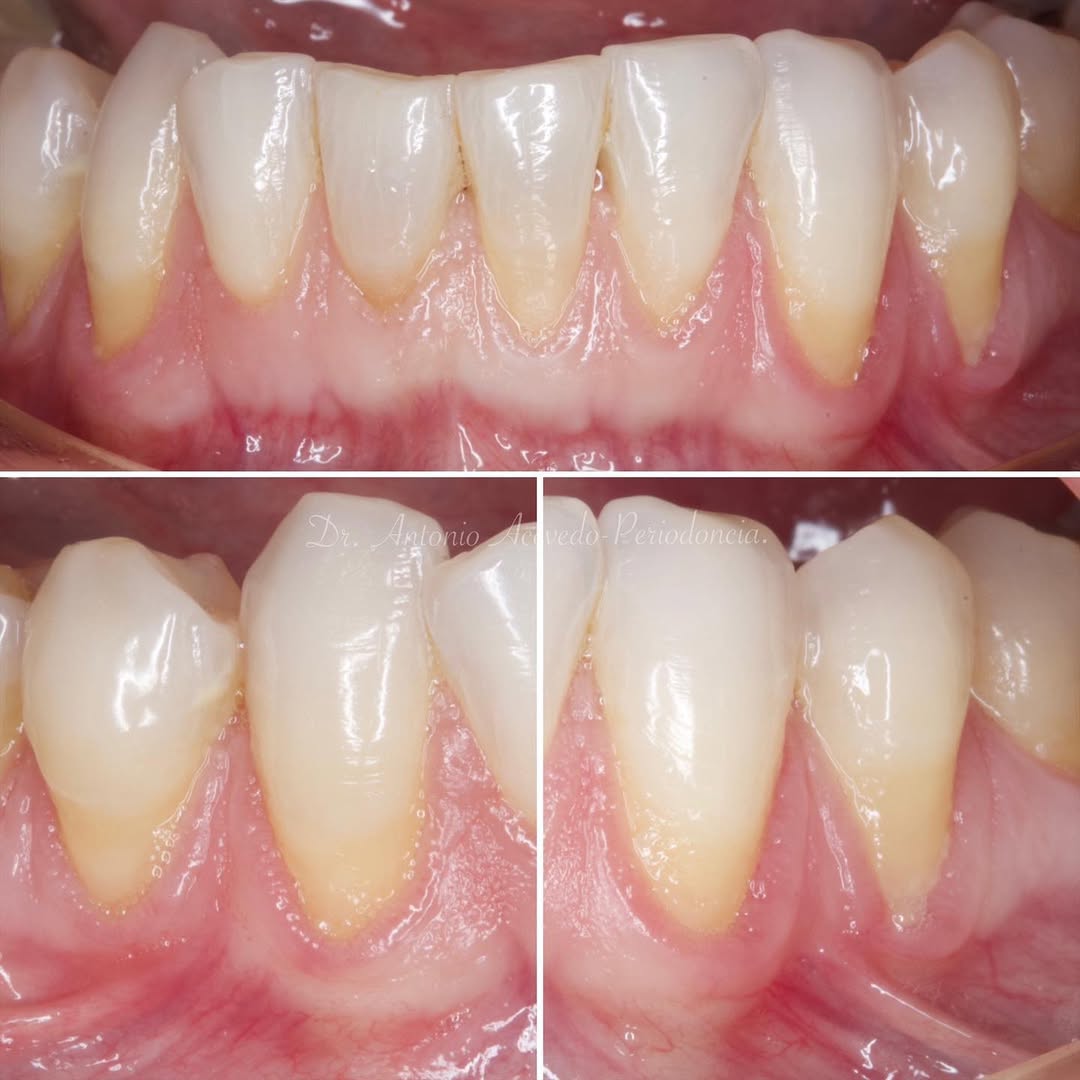

Durante una mañana, asistirás a una Cirugía Mucogingival de recubrimiento radicular de recesiones múltiples en IV y V sextante (36 a 43).

Gracias al uso del microscopio y a la proyección en tiempo real en pantalla, verás exactamente lo mismo que veo yo durante la cirugía, sin tener que estar

Aprende la planificación y técnica de la cirugía Mucogingival para el recubrimiento de recesiones y aumento de banda queratinizada en el sector anteroinferior

Durante una mañana, asistirás a una Cirugía Mucogingival de recubrimiento radicular de una recesión unitaria en 31 con frenillo asociado. Gracias al uso del microscopio y a la proyección en tiempo real en pantalla, verás exactamente lo mismo que veo yo durante la cirugía, sin tener que estar